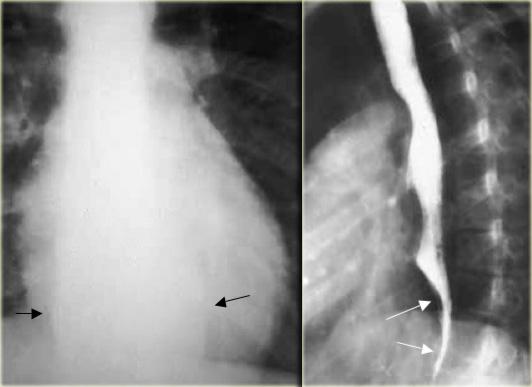

TRÁI: Hẹp đoạn xa dài và không đều do ung thư. PHẢI: Hẹp đoạn xa không có dạng thuôn nhọn và ở vị trí gần hơn so với co thắt tâm vị. Sự không đều (mũi tên) tại vị trí hẹp tinh tế nhưng dai dẳng.

Ngoài cùng bên trái là hình ảnh bệnh nhân ung thư có hẹp thực quản.

Hẹp không đều, không đối xứng gợi ý mạnh đến ung thư.

Hẹp thuôn nhọn đều đặn, đối xứng là đặc trưng của nguyên nhân lành tính, tuy nhiên các hẹp ác tính cũng có thể có đặc điểm tương tự và bắt chước tổn thương lành tính.

Kế bên là hình ảnh bệnh nhân ung thư có hẹp thực quản giống co thắt tâm vị.

Bệnh lý ác tính đoạn thực quản xa có thể rất giống co thắt tâm vị.

Nếu nhu động thực quản bình thường, có thể loại trừ co thắt tâm vị.

Tuy nhiên, nếu bất thường, các đặc điểm hình ảnh tinh tế như: hẹp không đối xứng, không đều, đột ngột hoặc ở vị trí cao, bất thường niêm mạc, hoặc bất thường cố định sẽ gợi ý chẩn đoán.

Bên trái là một trường hợp giả co thắt tâm vị khác.

Hẹp đoạn xa mô phỏng co thắt tâm vị, nhưng vị trí hẹp lệch tâm, các bờ vai không đối xứng (mũi tên), và niêm mạc không đều tại đỉnh vùng hẹp.

CT cho thấy thành đáy vị dày lên (mũi tên) do ung thư biểu mô tuyến.